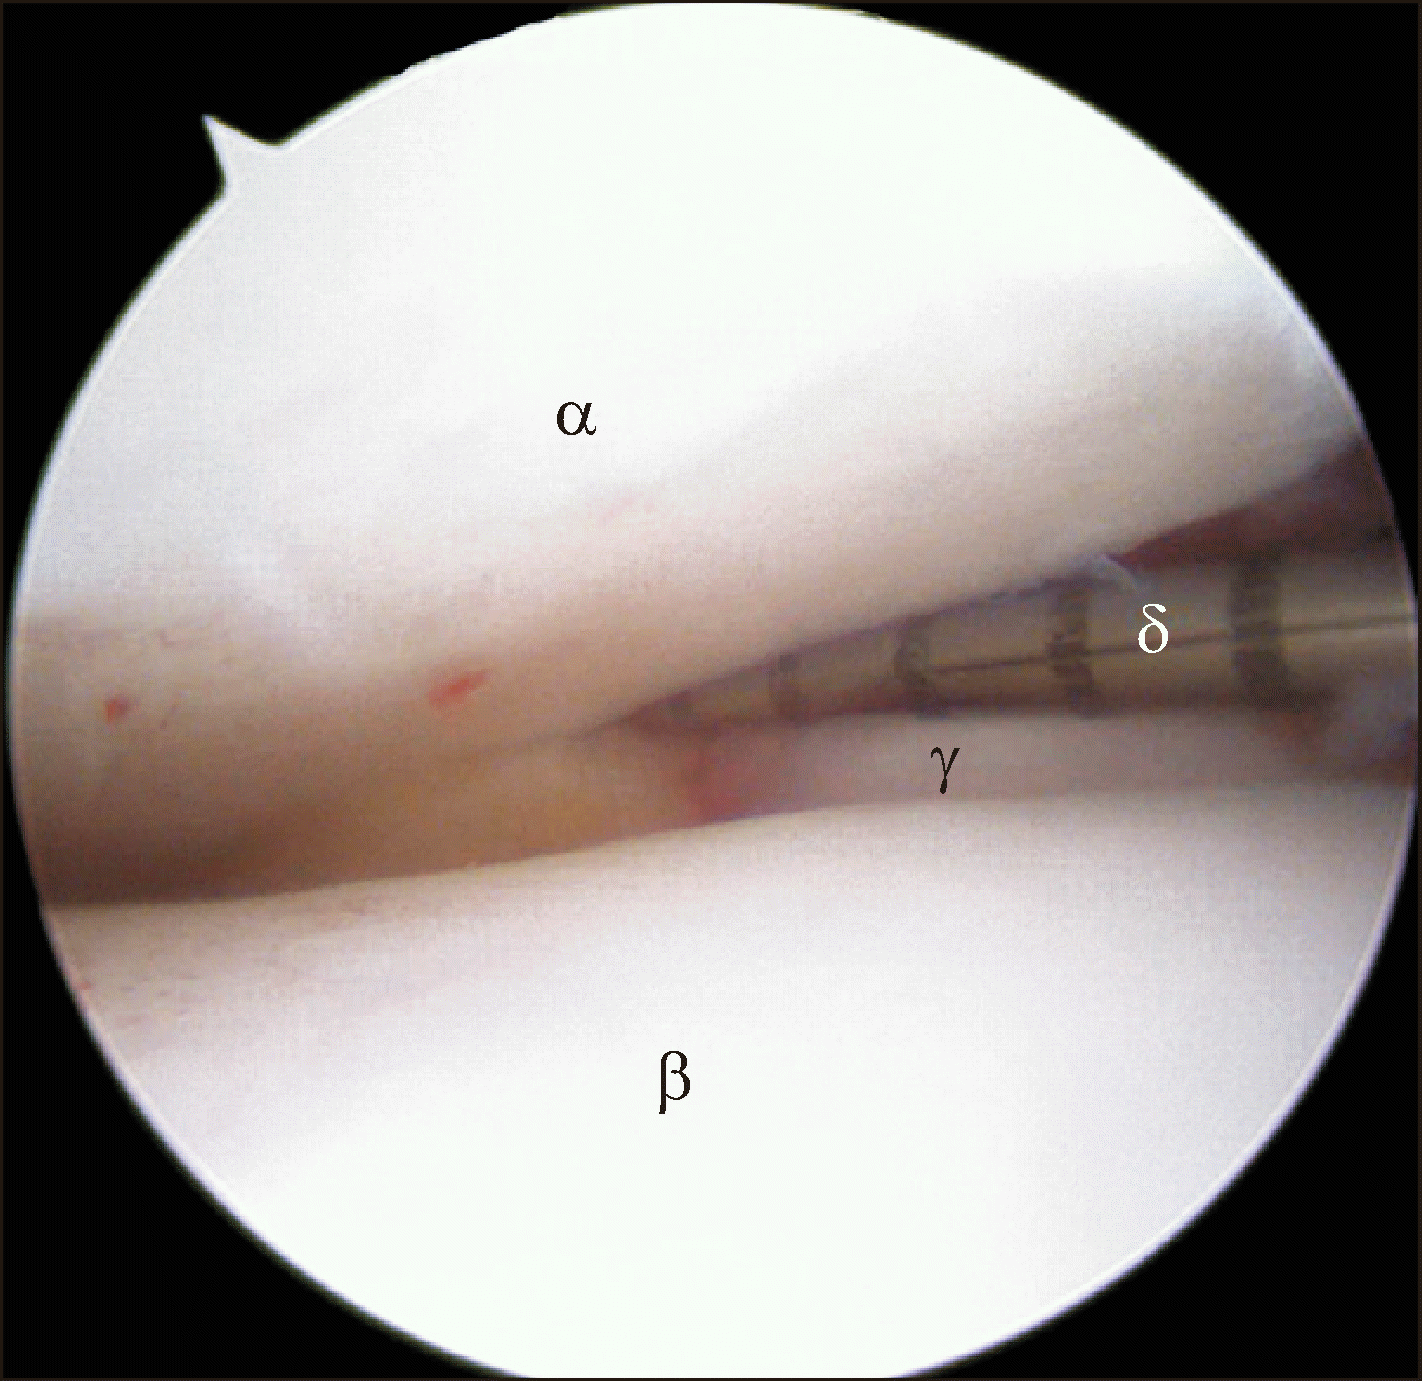

Figure 3

A widening of 2 mm or more, into which an arthroscopic probe can be inserted during arthroscopic examination, indicates a syndesmosis injury. αTibia, βTalus, γFibula, δArthroscopic probe.